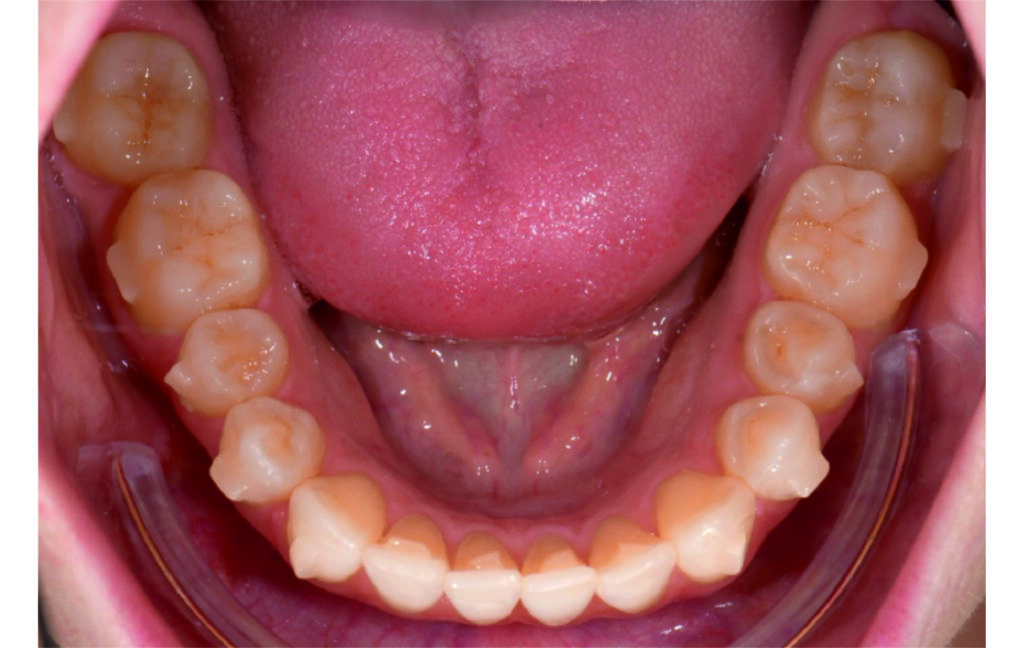

Initial Photos and datas

Angle Class II 2mm on the right, Angle Class II 2mm on the left, light mandibular asymmetry to the right, lower central line 1mm to the right, upper central line 1,5mm to the left, 1mm overjet and overbite. Sagittal asymmetry of upper dental arch. Light crowding upper and lower frontal segments, severe attrition of posterior teeth, night bruxism. Normal sagittal position of both jaws, high angle case, steep mandibular ramus,excessive lower facial height, open bite tendency.

The case initially presented as a moderate Class II on the right and a Class II tendency on the left, with tapered dental arches and an anterior open bite extending to tooth 26 in segment II.

In segment I, the open bite reached up to the first premolar.